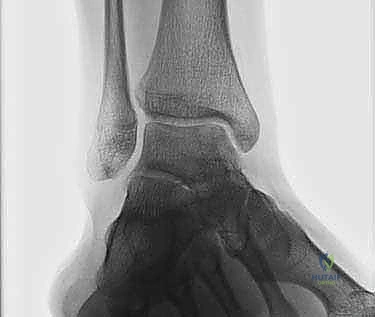

- الأشعة السينية (X-rays): تُستخدم كخطوة أولى لاستبعاد الكسور العظمية الكبيرة والتهاب المفاصل المتقدم. في بعض الأحيان، يمكن رؤية "ظل" أو كيس عظمي يشير إلى وجود آفة.

- التصوير بالرنين المغناطيسي (MRI): هو المعيار الذهبي (Gold Standard) لتشخيص OLTs. يُظهر الرنين المغناطيسي الغضروف بدقة عالية، ويحدد حجم الآفة، عمقها، وحالة العظم تحت الغضروفي (مثل وجود وذمة عظمية - Bone Marrow Edema).

- الأشعة المقطعية (CT Scan): يطلبها الدكتور هطيف أحياناً للحصول على خريطة ثلاثية الأبعاد دقيقة للعظم، مما يساعد في التخطيط الجراحي وتحديد حجم الرقعة العظمية المطلوبة للزرع.